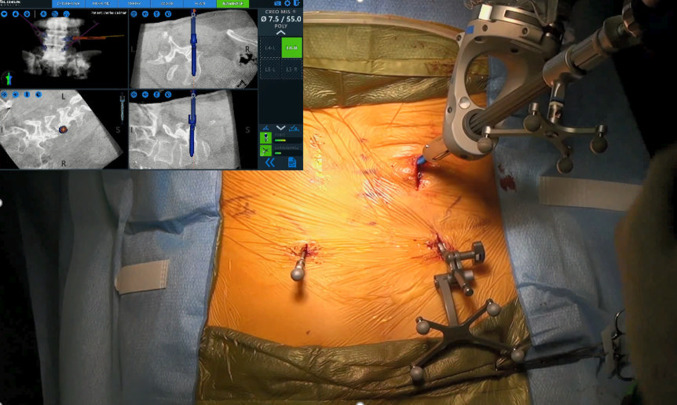

Navigated robot-assisted pedicle screw positioning system

The robotic positioning system (ExcelsiusGPS®; Globus Medical, Inc., Audubon, PA, USA) uses radiological patient images (preoperative CT, intraoperative CT, or fluoroscopy), along with a dynamic reference base and positioning camera to guide pedicle screw placement in real time. Robotic assistance can help guide the surgeon’s planning and approach prior to and during surgery, and is designed to improve pedicle screw accuracy.

Surgical technique: minimally invasive navigated robot-assisted surgery

In this study, the robotic system operated on one functional modality, intraoperative CT. The image coordinate system was obtained from a portable intraoperative CT (e.g., O-arm, Medtronic SNT, Louisville, CO, USA) or a standard CT scan taken at the time of surgery with the patient already in surgical position (prone). After a CT scan was taken and the spinal levels identified, pedicle screw trajectories were planned and saved. Reference frames were installed and fixated to the pelvis, and instruments and arrays with reflective markers were registered. A surgeon-controlled foot pedal activated and positioned the robot arm to the planned pedicle trajectory. Stab incisions were made on the skin using a scalpel. Pedicle screws were inserted percutaneously using navigated instruments guided by the robotic arm. Per case, one attending spine surgeon and one resident performed pedicle screw placement consistently on either the left or right side. This sequence was repeated until all pedicle screws were placed. Rods were then placed and locking caps were set once the rods were in the proper position. Intraoperative CT images were taken to verify screw and rod position. Interbody devices when used were inserted manually. Surgical incisions were cleaned and closed in the standard fashion.

A CT-based Gertzbein and Robbins System (GRS) was used to classify pedicle screw accuracy, in which screws were graded as A (screw is completely within the pedicle), B (pedicle cortical breach < 2 mm), C (pedicle cortical breach < 4 mm), D (pedicle cortical breach < 6 mm), and E (pedicle cortical breach > 6 mm) [4]. The evaluator was blinded to the study groups. Screws with an A or B grade were deemed as accurate while screws with a C, D, or E grade were considered inaccurate, as previously demonstrated [4–7]. The number of accurate screws divided by the number of total screws placed with robotic navigation resulted in an accuracy percentage for the first 101 cases. Additionally, quantitative three-dimensional screw tip, screw tail, and screw angulation offsets were determined using CT scans and image overlay analysis to compare preoperative planned trajectories to actual postoperative screw placement (Fig. 1). Pedicle screw malposition, reposition, and return to operating room (OR) rates were collected.

Lumbosacral pedicle screw planning and placement with a minimally invasive navigated robot-assisted pedicle screw positioning system